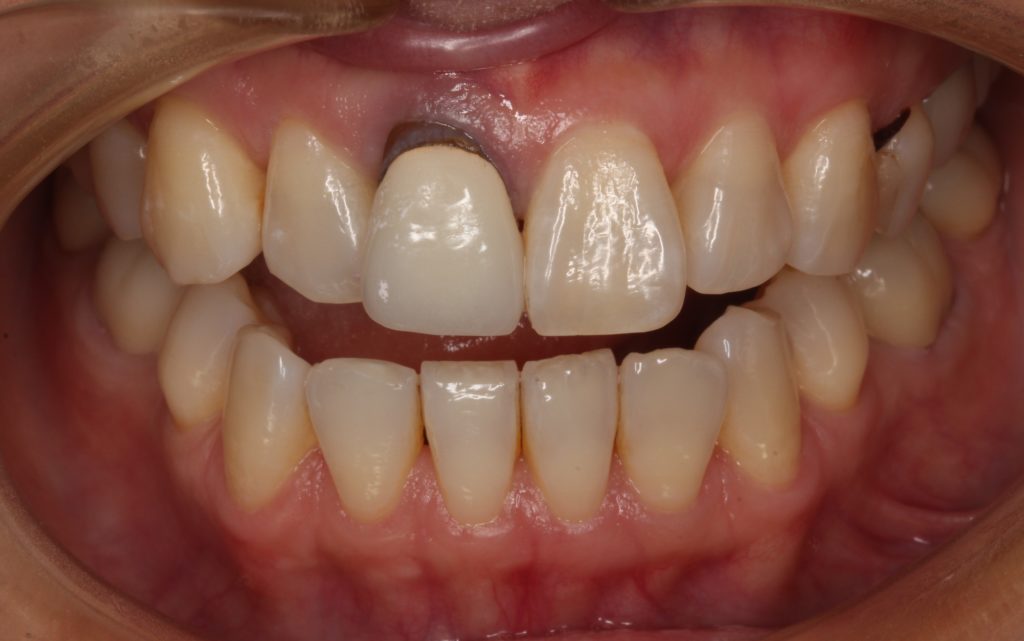

被せ物を外した歯です。

歯が全体的に黒く変色しています。

根元は、被せ物を外すと良く分かりますが自身の歯の根元が出ていたのが分かります。

先端は銀色のメタルコアが見えています。